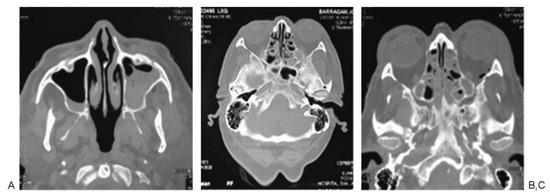

According to Manson’s classification, 17.9% (n ¼ 38) of the trauma in the group corresponded to high-energy trauma, followed by medium-energy trauma at 33.5% (n ¼ 71) and low-energy trauma at 48.6% (n ¼ 103). Among the patients with high-energy trauma, 31.5% (n ¼ 12) had combined fractures of the sphenoid bone and sphenoid sinus and 31.5% (n ¼ 12) had sphenoid sinus fractures only. In contrast, 1.4% (n ¼ 3) of patients with middle-energy trauma had sphenoid bone fractures, 5.6% (n ¼ 4) of the patients had sphenoid sinus fractures, and 4.2% (n ¼ 3) of the patients had sphenoid bone and sphenoid sinus fractures. In the low-energy trauma group, only 1 patient presented sphenoid sinus fracture (0.97%; Table 3; Figure 2, Figure 3 and Figure 4).

Figure 3. Patient 2: high-energy comminuted fracture of nasal bone (A and B), associated fracture of the sphenoid sinus.

Figure 4. Patient 3: slightly displaced malar fracture in a patient with medium energy trauma, (A) presence of fracture at the level of the zygomatic arch, (B and C) fracture at the lateral wall of the sphenoid bone and orbital fracture associated.